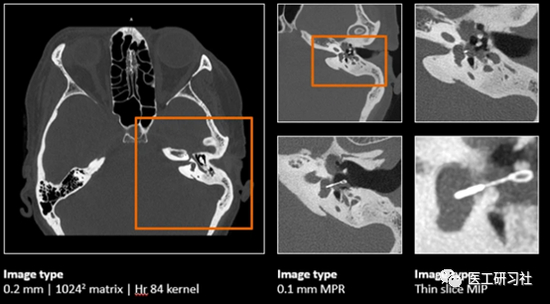

得益于探测器结构优势,光子计数CT的等效探测器层厚高达0.2mm;加上其不需要闪烁体将X线转换成可见光,没有光横向扩散影响,可以实现更高空间分辨率成像;此外,光子计数CT通过通过设置阈值实现光子脉冲数计数,可以消除暗电流导致的假计数,大大降低了电子噪声。

因此,光子计数CT可以获得极高的空间分辨率、较强的低密度分辨率、超低的图像噪声,其阅片质感也和常规能量积分CT不同。

光子计数CT的高分辨率内耳成像(来自网络)

不过,目前超高端CT的空间分辨率已经非常高,光子计数CT能提供的可视化分辨率能达到30LP/cm、40LP/cm、还是50LP/cm?

更何况,能量积分CT领域早已诞生了超高分辨CT,比如佳能Aquilion Precision,其2048×2048重建矩阵、50lp/cm@0%MTF的超高分辨CT;比如,北京友谊医院参与研发的耳鼻喉专用CT,分辨率甚至可达50μm。